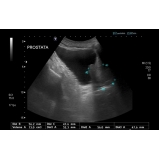

Procurando por biopsia de próstata? A urologia é uma especialidade da medicina que trata problemas do sistema urinário masculino e feminino, tratando também do sistema reprodutor masculino. Através da biópsia de próstata o médico Urologista pode obter amostras do tecido prostático, com o objetivo de identificar células cancerígenas. Para manter a saúde em dia é imprescindível realizar consultas periódicas ao médico para que seja feita uma avaliação.